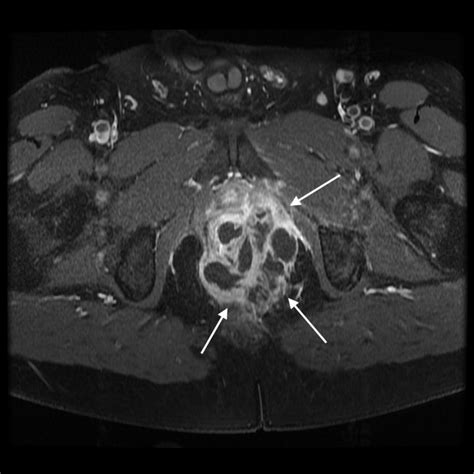

Diagnosing a perianal abscess typically involves a physical examination by a healthcare provider. The doctor will examine the affected area and may ask about symptoms and medical history. In some cases, additional tests may be necessary to confirm the diagnosis or rule out other conditions. These tests may include:

• Imaging Tests: Such as an ultrasound or CT scan to visualize the abscess and surrounding tissues.

Perianal Abscesses Pictures

Visual aids can be incredibly helpful in understanding medical conditions. While it’s important to note that viewing perianal abscesses pictures can be graphic and may not be suitable for all audiences, they can provide a clear understanding of what these abscesses look like. These images often show the redness, swelling, and drainage associated with the condition. If you are considering viewing such images, it is advisable to do so under the guidance of a healthcare professional.